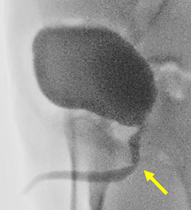

頚部リンパ管腫に対して硬化治療が奏功した一例

胎児超音波検査で頚部リンパ管腫を指摘されていた症例で、生後4か月時に病変が急速に増大して、呼吸困難で受診、外来で緊急気管挿管・緊急入院となりましたが、透視下に硬化療法を行ったところ、嚢胞性病変のほとんどが潰れて、治療後は腫れなくなり、元気に過ごしています。

圧迫して呼吸促迫になったため緊急気管挿管

(左頚部から縦隔に広がる病変)

病変内に注入し、透視で病変への広がりを

リアルタイムに確認。CT画像で指摘された

病変に一致して薬剤が広がった。

頚部の腫瘤はほとんど目立たなくなった。